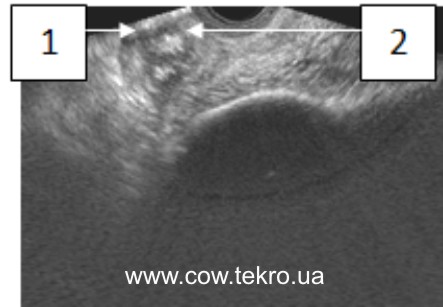

За ультразвукового дослідження у яєчниках візуалізується неоднорідна ехоструктура тканин, ущільнення кіркового шару гонад у вигляді ехопозитивної ділянки, без везикулярних фолікулів і жовтих тіл (рис. 4).

Рисунок 4 – Ехограма яєчника за гіпотрофії: 1 – тканини яєчника; 2 – ехопозитивна ділянка.